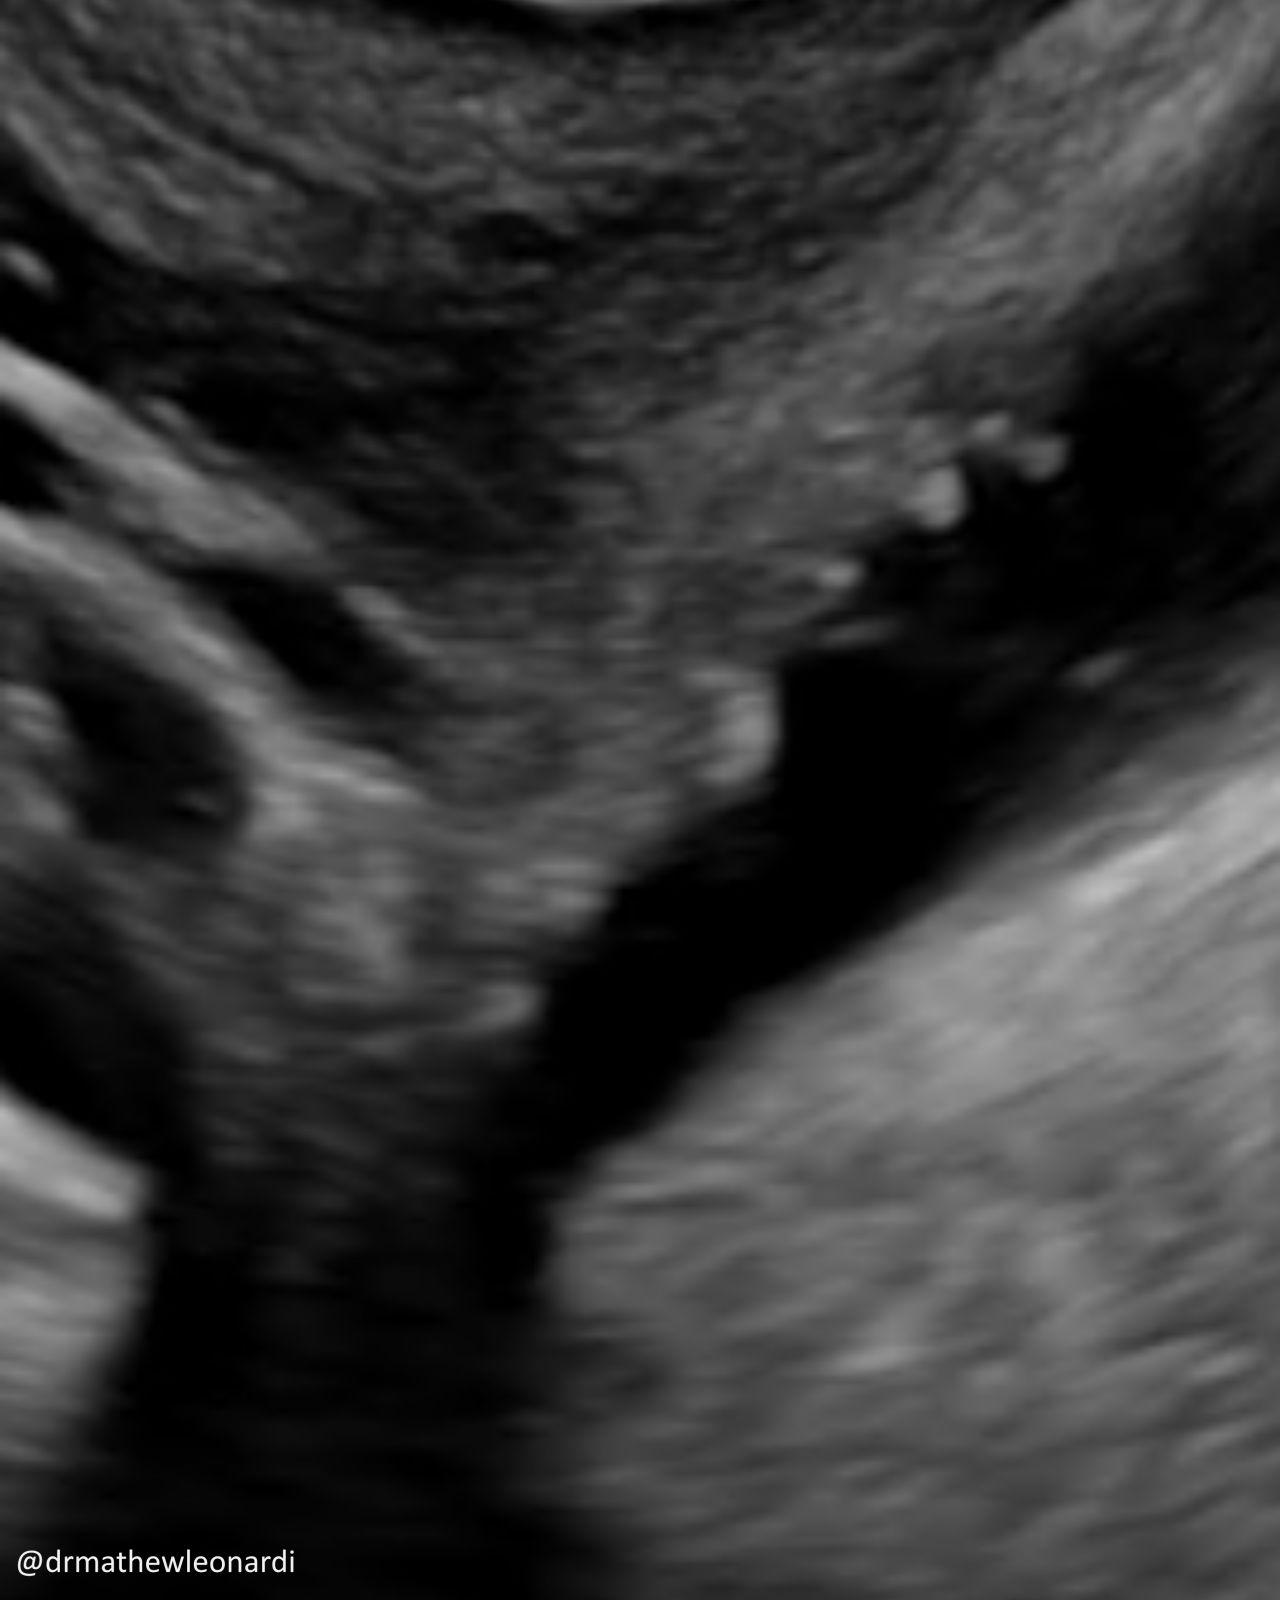

“Endometriosis does not have one single appearance, and that is part of why it is so often missed.

In this carousel, I’ve included a range of endometriosis lesions across different disease types and locations, including superficial disease, ovarian disease, and deep endometriosis involving areas such as the bowel, bladder, uterosacral ligaments, peritoneum, vagina, and ovary. A few are deliberately difficult because real-life recognition is not always straightforward.